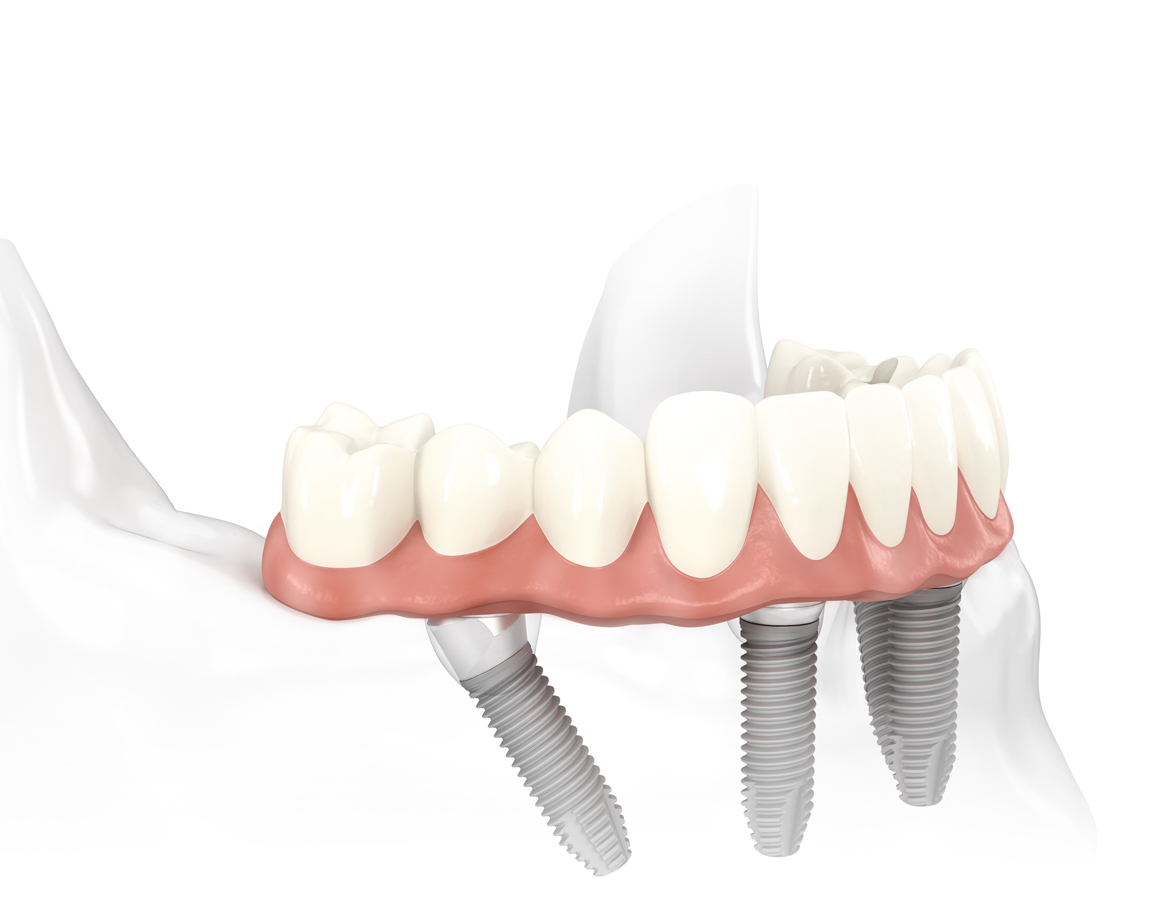

Технология all-on-4 или «Все на 4х» позволяет решить такую проблему, как полное отсутствие зубов. Технология восстановления зубного ряда «все на четырех» - инновационный метод, отличающийся высокой надежностью, эффективностью и быстрым периодом адаптации. Будущий протез фиксируется на 4х установленных в челюсть имплантатах. Нагрузка распределяется равномерно на импланты, и это позволяет зафиксировать надежно будущий протез, не доставляя пациенту никакого дискомфорта.

Суть данного вида протезирования заключается в установке 4х дентальных имплантов на одну челюсть, на которые уже крепится несъемный протез. Два из четыре имплантов устанавливаются во фронтальном (переднем) отделе костной ткани, а два оставшиеся в боковом или дистальном отделе и устанавливаются под углом 45°. Дистальный отдел - это задняя область в которой находятся коренные зубы «моляры» по 3 зуба с каждой стороны челюсти. При таком методе нагрузка от несъёмного протеза распределяется равномерно по челюсти и не вызывает осложнений в последствии.

Для фиксации протеза на имплантатах установленных в дистальном отделе под углом используется специальный наклонный мультиюнит-абатмент. Такая особенная конструкция позволяет крепить протез на импланте под 45 градусов с очень высокой степенью надежности.